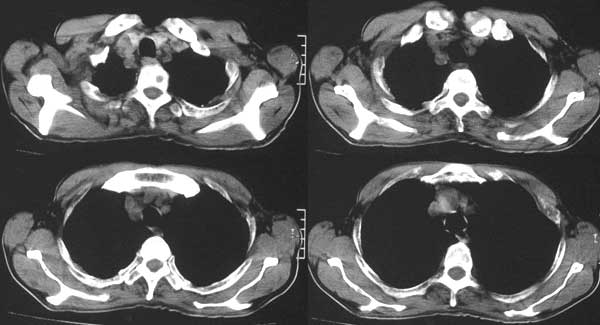

患者,男79岁,左侧肾癌术后5个月。近三个月,咳嗽时有痰中带血。

本例病人肺内多发结节灶、双侧肋骨破坏、胸椎椎体及椎弓破坏应是肾癌转移。请大家分析气管内结节灶性质?另外还得麻烦领导给删掉那多余的那幅图。谢谢了!

双肺多发结节状影,腹膜后见肿大淋巴结,支持肾ca转移

支持肺内 肋骨 椎体转移。

支持肺内,椎体,肋骨,腹膜后淋巴转移.

气管内结节灶性质是粘痰核?因为纵隔窗看不见

手术是怎么做的,好像没做。右肾还有两个病灶。气管腔内的那个结节密度确实很低,考虑粘痰核应该没问题,若是新生物不会这么低。不过挂在前壁上了,少见!

双肺内多发结节影是转移灶没问题,气管内的还应该商榷

肺内 肋骨 椎体转移已确定,气管内阴影不象结节,气管内壁无增生,显示层面只有一层,纵隔窗见不到,多考虑粘痰核.